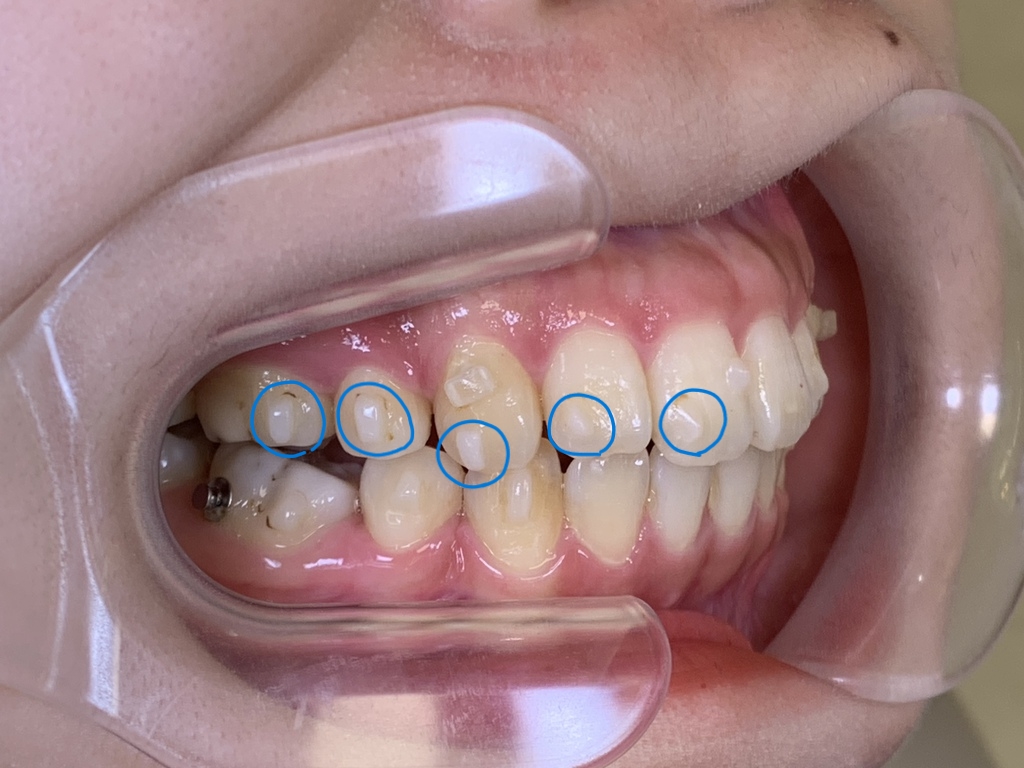

インビザライン治療を行う上で欠かせないアタッチメント(青丸で囲んでいる白い突起物の事です)

歯の表面にこのアタッチメントを付けることで、歯により強く力を加えていくことができます。

アタッチメントが外れていると、その分マウスピースと歯に隙間ができるので十分に歯を捕まえきれず、少しずつマウスピースがふわ~と浮いてきてしまいます💧

浮きはこんな感じです。